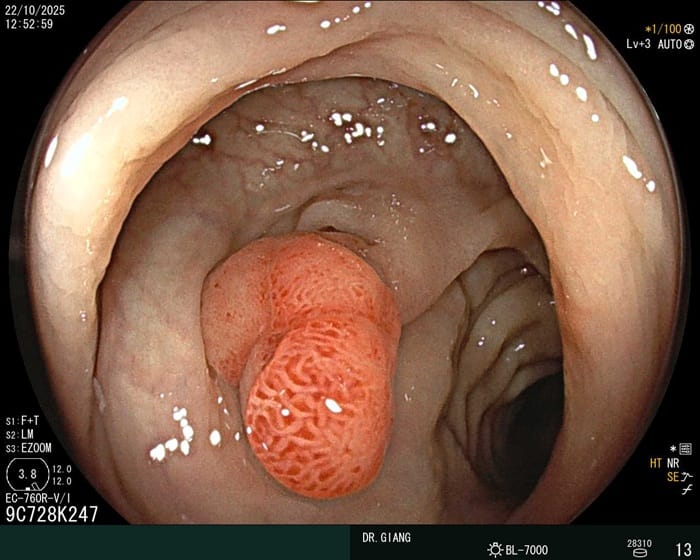

Viêm đại tràng mạn tính

Với thể mạn, niêm mạc đại tràng dày, mất độ bóng, có mảng xơ trắng hoặc loét rải rác. Một số đoạn đại tràng có thể co hẹp hoặc biến dạng nhẹ.

Niêm mạc dạ dày co thắt, có xuất hiện polyp khi quan sát nội soi

Bệnh thường gây đau bụng âm ỉ, rối loạn tiêu hóa kéo dài, dễ tái phát. Cách điều trị chủ yếu là kiểm soát chế độ ăn uống, dùng thuốc điều hòa nhu động ruột, bổ sung men vi sinh và theo dõi định kỳ.